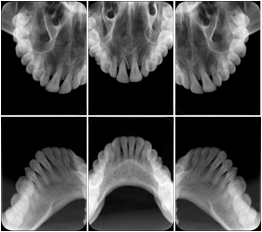

2. A patient requests cosmetic surgery to enhance their facial appearance. The case requires consultation between an orthodontist in New York and an oral surgeon in California. The cephalometric series of 2D projections constructed from the volumetric CT data that is used for the discussion is arranged by a Structured Display for transfer between the two practitioners.

Cephalometric Series Structured Display

Figure OO-2. Cephalometric Series Structured Display

3. A dental provider wishes to capture a series of DICOM IO images for the patient’s dentition. The tooth morphology, teeth are divided into molars, premolars, canines and incisors, and a number of images for each jaw. The anatomic information was captured utilizing the triplet of schema. This standard code sequence is based on ISO 3950-2010, Dentistry - Designation system for teeth and areas of the oral cavity.

In most standard cases, images are oriented in structured layouts. These structured displays are useful to be shared between providers for reference purposes.

Table OO.1.1-1 shows structured display standard templates, where Viewset ID is based on the Japanese Society for Oral and Maxillofacial Radiology (JSOMR) classification provided by JIRA (Japan Medical Imaging and Radiological Systems Industries Association, www.jira-net.or.jp). Expected or typical teeth to be imaged location, region and designation codes are based on ISO 3950-2010, Dentistry - Designation system for teeth and areas of the oral cavity. For all the hanging protocols listed in OO.1.1-1, the value to use for Hanging Protocol Creator (0072,0008) is "JSOMR" and the value to use for Hanging Protocol Name (0072,0002) does not include "JSOMR" (e.g., "DL-S001A", not "JSOMR DL-S001A").